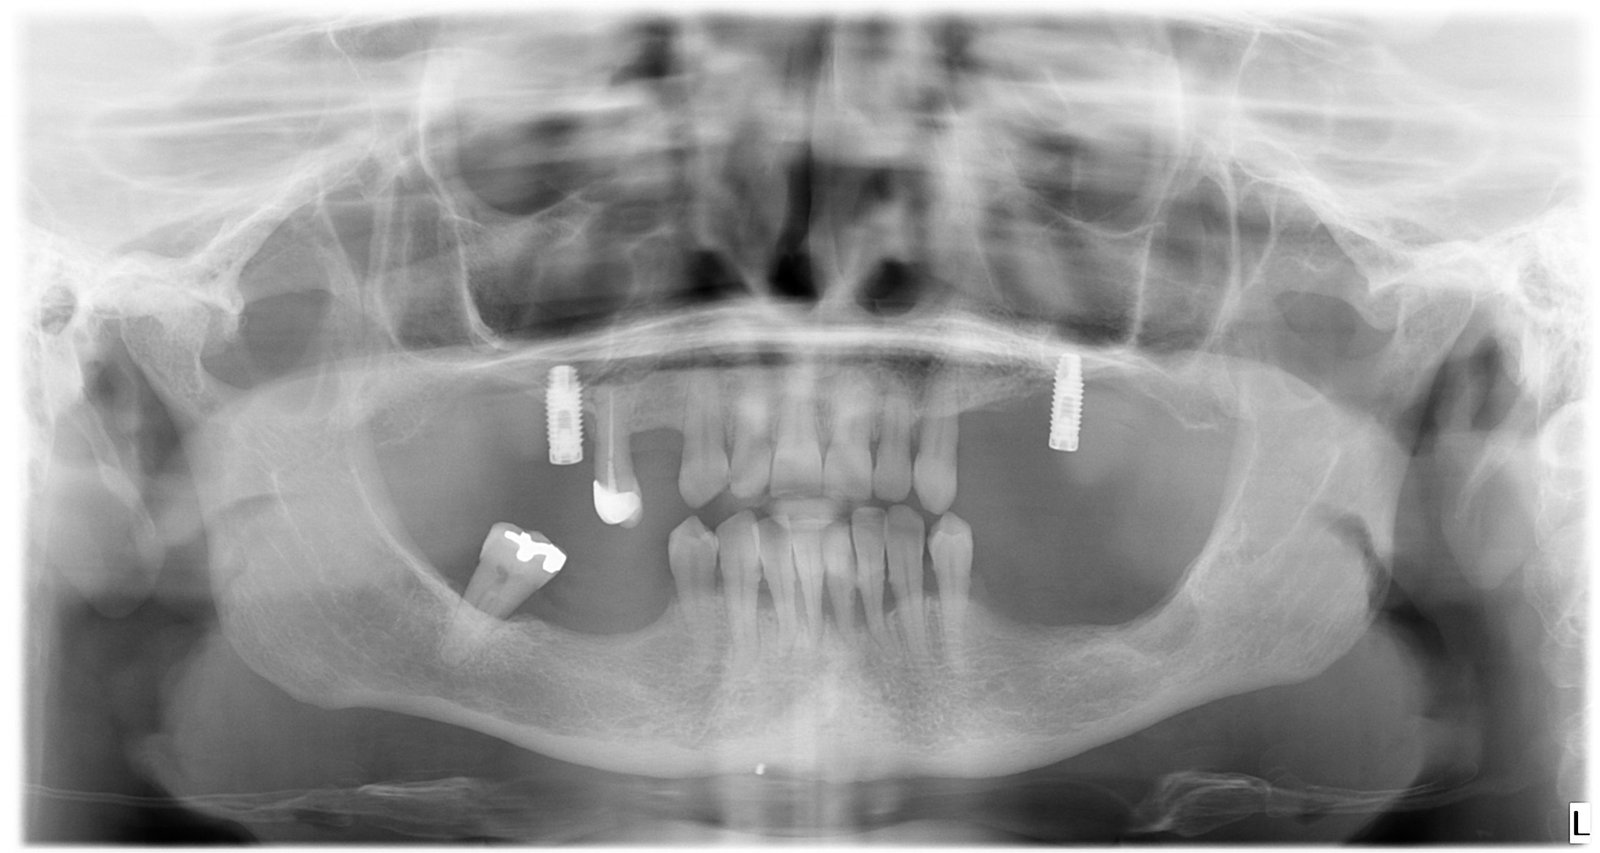

Caso 1 - caso de Carga inmediata

La paciente acudió con la necesidad de recuperar sus dientes de forma rápida y sin largos tiempos de espera. Gracias a la técnica de carga inmediata, colocamos dientes fijos el mismo día, devolviéndole su sonrisa de manera inmediata y segura.

Esta imagen muestra la planificación precisa del tratamiento de carga inmediata, clave para garantizar estabilidad desde el primer momento.